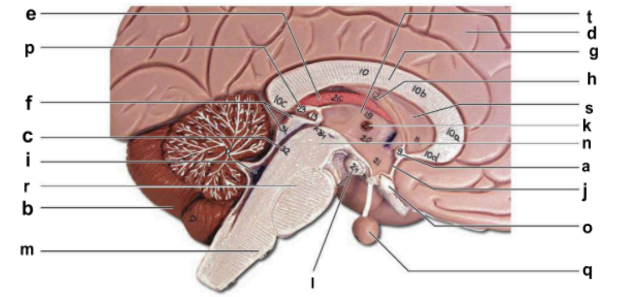

Identify the structure labeled “a” in the image.

anterior commissure

Identify the structure labeled “b” in the image.

cerebellum

Identify the structure labeled “c” in the image.

cerebral aqueduct

Identify the structure labeled “d” in the image.

cerebral hemisphere

Identify the structure labeled “e” in the image.

choroid plexus

Identify the structure labeled “f” in the image.

corpora quadrigemina

Identify the structure labeled “g” in the image.

corpos callosum

Identify the structure labeled “h” in the image.

fornix

Identify the structure labeled “i” in the image.

fourth ventricle

Identify the structure labeled “j” in the image.

hypothalamus

Identify the structure labeled “k” in the image.

interthalamic adhesion

Identify the structure labeled “l” in the image.

mammilary body

Identify the structure labeled “m” in the image.

medulla oblongata

Identify the structure labeled “n” in the image.

midbrain

Identify the structure labeled “o” in the image.

optic chiasma

Identify the structure labeled “p” in the image.

pineal gland

Identify the structure labeled “q” in the image.

pituitary gland

Identify the structure labeled “r” in the image.

pons

Identify the structure labeled “s” in the image.

septum pellucidum

Identify the structure labeled “t” in the image.

thalamus